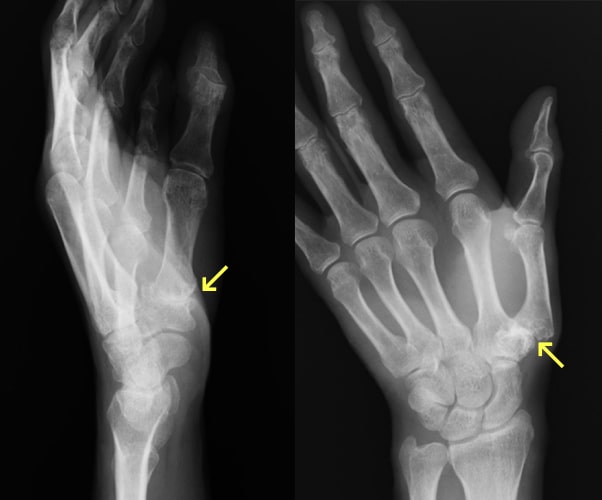

指骨・中手骨骨折

指骨・中手骨骨折写真

基節骨変形癒合により指交差現象が出現

(握ると環指が小指に重なる)

原因

壁を殴ってしまったり、転倒した際に強打してしまったりして生じます。

症状

手や指が腫れて、痛くて動かせなくなります。変形を認める場合もあります。

治療方針

転位やズレの程度で治療方針を決めます。指の骨折の治療で重要なことは長期間固定をして拘縮を作らないことです。ほんの数週間の外固定により骨折部以外の関節も固くなってしまい、また少しの変形であっても指を握った時に重なったりする重篤な後遺症が生じることがありますので注意が必要です。手外科専門医にかかることをお勧めします。